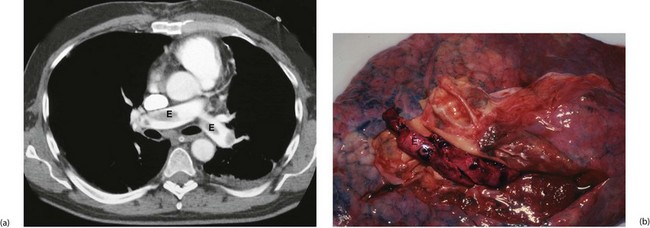

Fig. 12.7 Pulmonary embolism

(a) Thoracic CT pulmonary artery scan (CTPA) with intravenous contrast showing large emboli E in the pulmonary arteries. This is the investigation of choice where there is a high suspicion of PE. (b) Post-mortem specimen of lung from a patient who died of massive pulmonary embolism. Embolic material has been removed, but some remains in the pulmonary arteries E